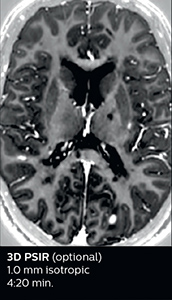

Fast MS protocol with optional sequences

The abbreviated MS protocol for brain is only around 9 minutes, so in case of suspected multiple sclerosis, one or two more advanced sequences may be added, such as PSIR (phase sensitive inversion recovery) or susceptibility-weighted sequences to help us make more confident diagnoses in these inflammatory cases.

In this example, the optional 3D multishot susceptibility weighted sequence with 0.6 mm isotropic voxels is 2 lesions with a central vein sign (arrows) and one lesion with a phase-rim sign (arrowhead). The total scan time, including SmartBrain and axial PD/T2 3mm, is 11:10 min. and is 18:30 min. with the optional 3D PSIR and 3D SWI multishot included.

3D TFE T1

3D FLAIR

DWI image

3D T1w TSE Gd

3D PSIR

3D SWI

“In multiple sclerosis patients, we increasingly include a multishot susceptibility sequence [3] in our routine cases, thanks to the shorter scan times. Our abbreviated MS protocol for brain is around 8 to 9 minutes, so we can ask for one or two additional sequences to visualize the central veins, or to get an additional contrast to better depict posterior fossa lesions. In cases of white matter lesions of unknown significance on FLAIR images, for example when we see high signal hyperintensities in the brain, we can add on more advanced sequences such as PSIR (phase sensitive inversion recovery) or susceptibility-weighted sequences to help us in distinguishing between MS and nonspecific or vascular abnormalities in these inflammatory cases.”